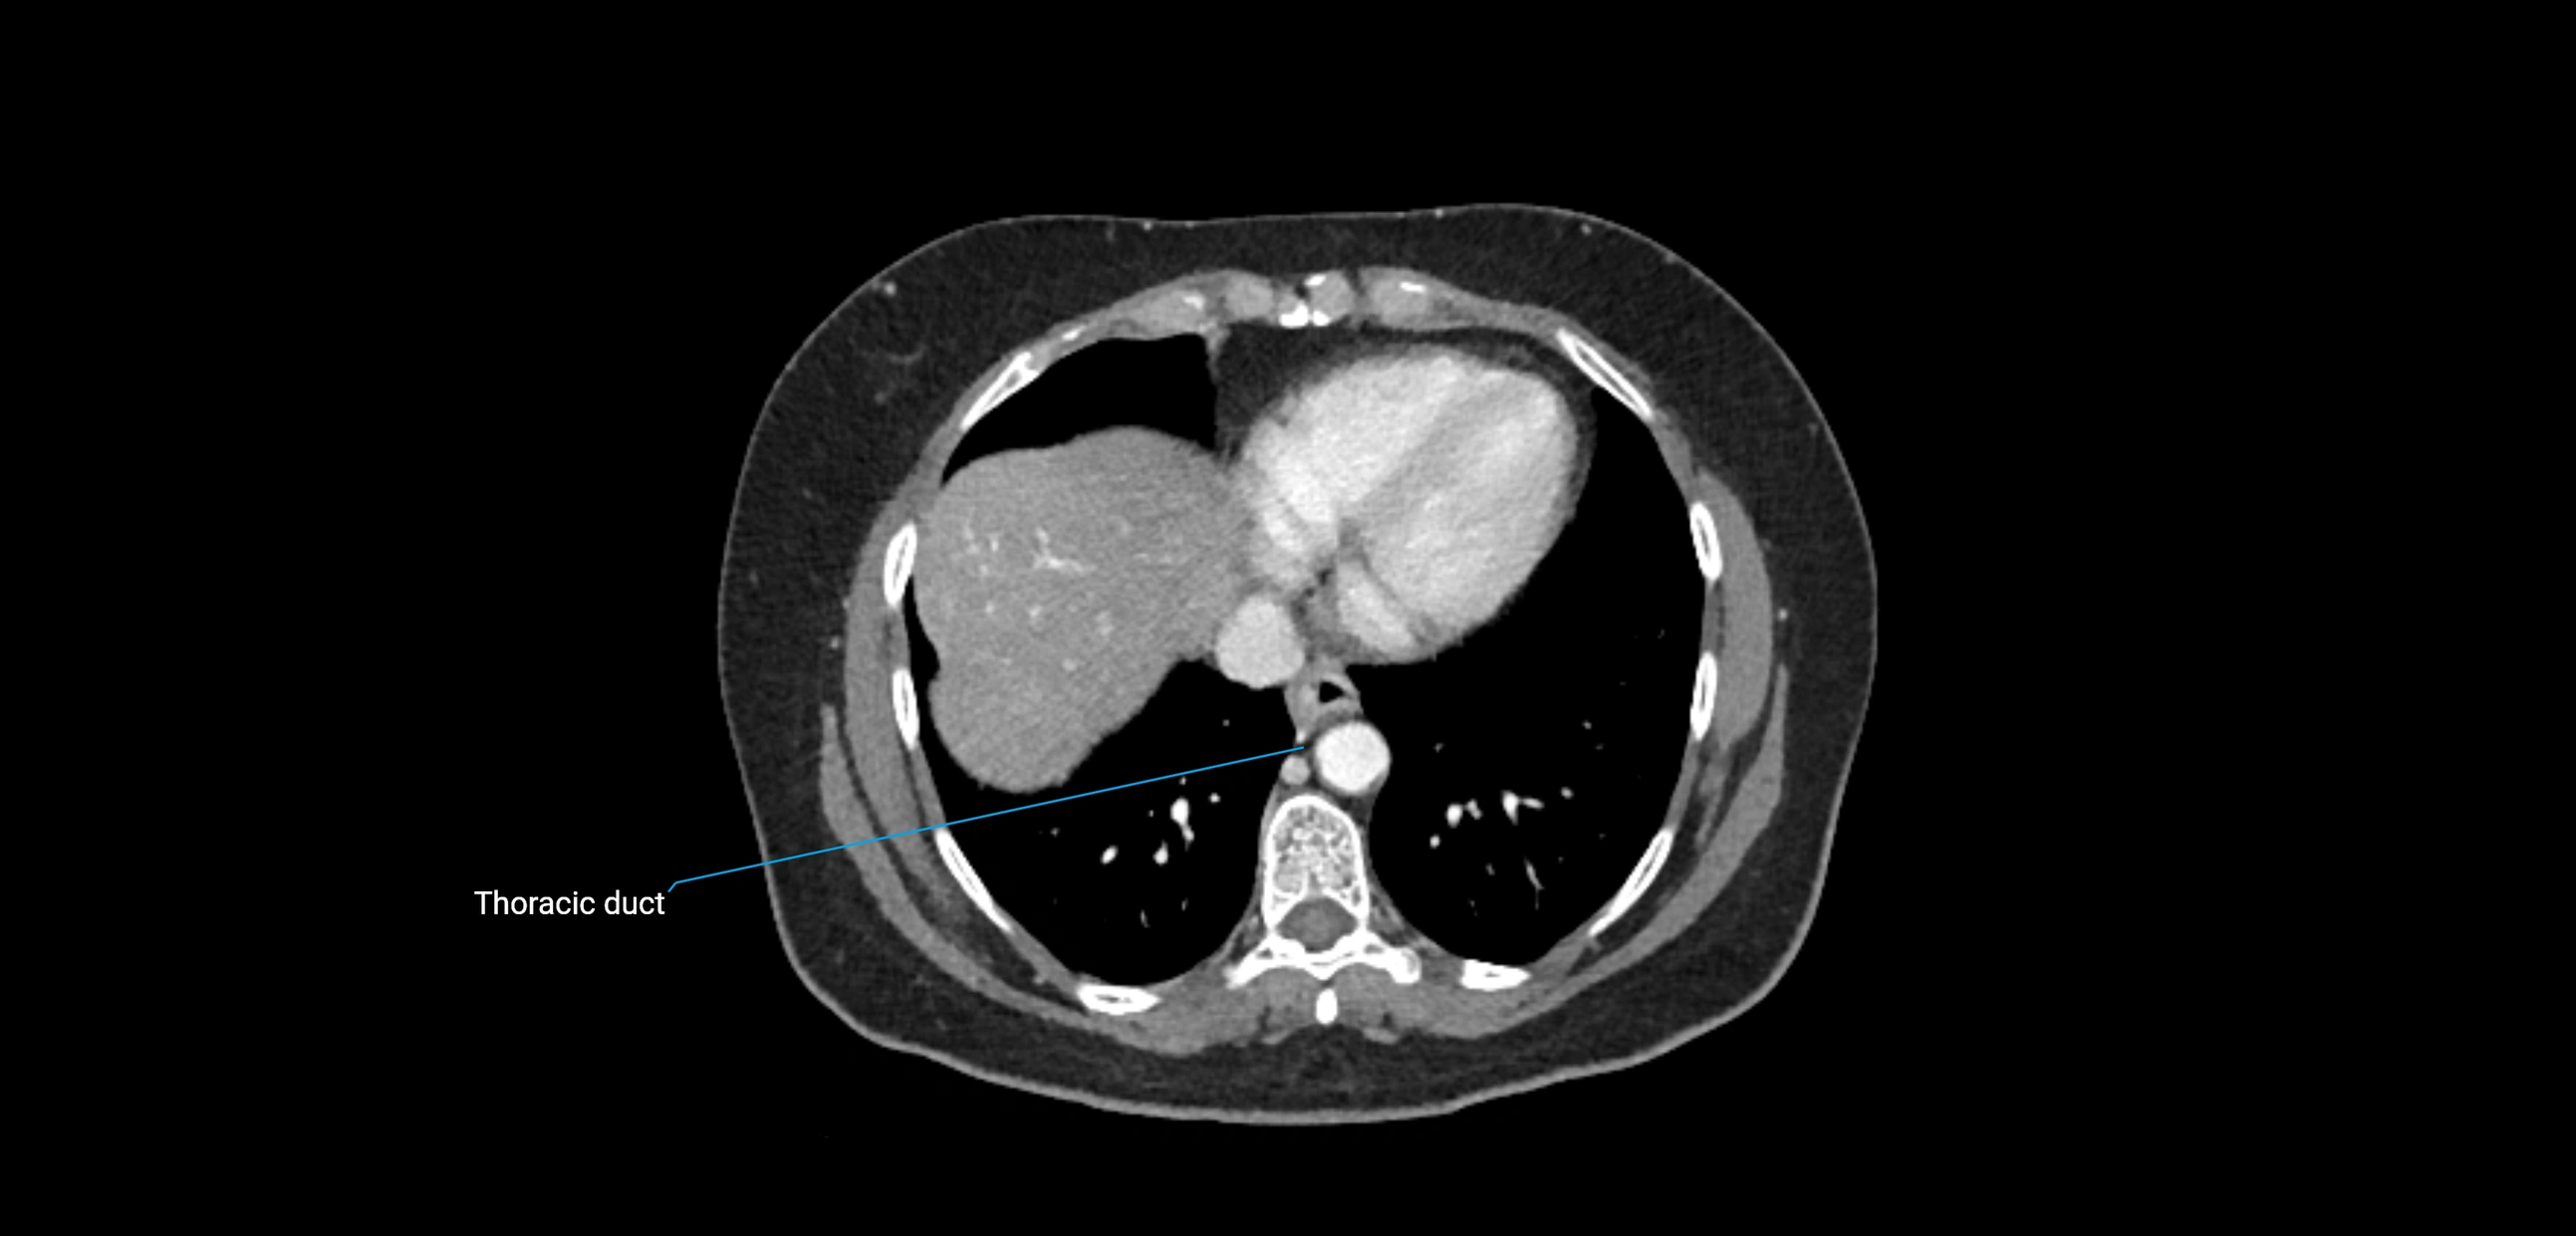

CT Appearance

CT Post-Contrast:

• Normal nodes enhance homogeneously

• Malignant nodes may show heterogeneous enhancement, central necrosis, or conglomerate formation

• Size >1 cm short axis is suspicious, though morphology and distribution are equally important

CT Venography (CTV):

• Demonstrates nodal encasement or compression of adjacent vessels (aorta, IVC, renal veins)

• Useful in staging testicular and ovarian malignancies

• Provides 3D reconstructions for retroperitoneal lymph node dissection planning